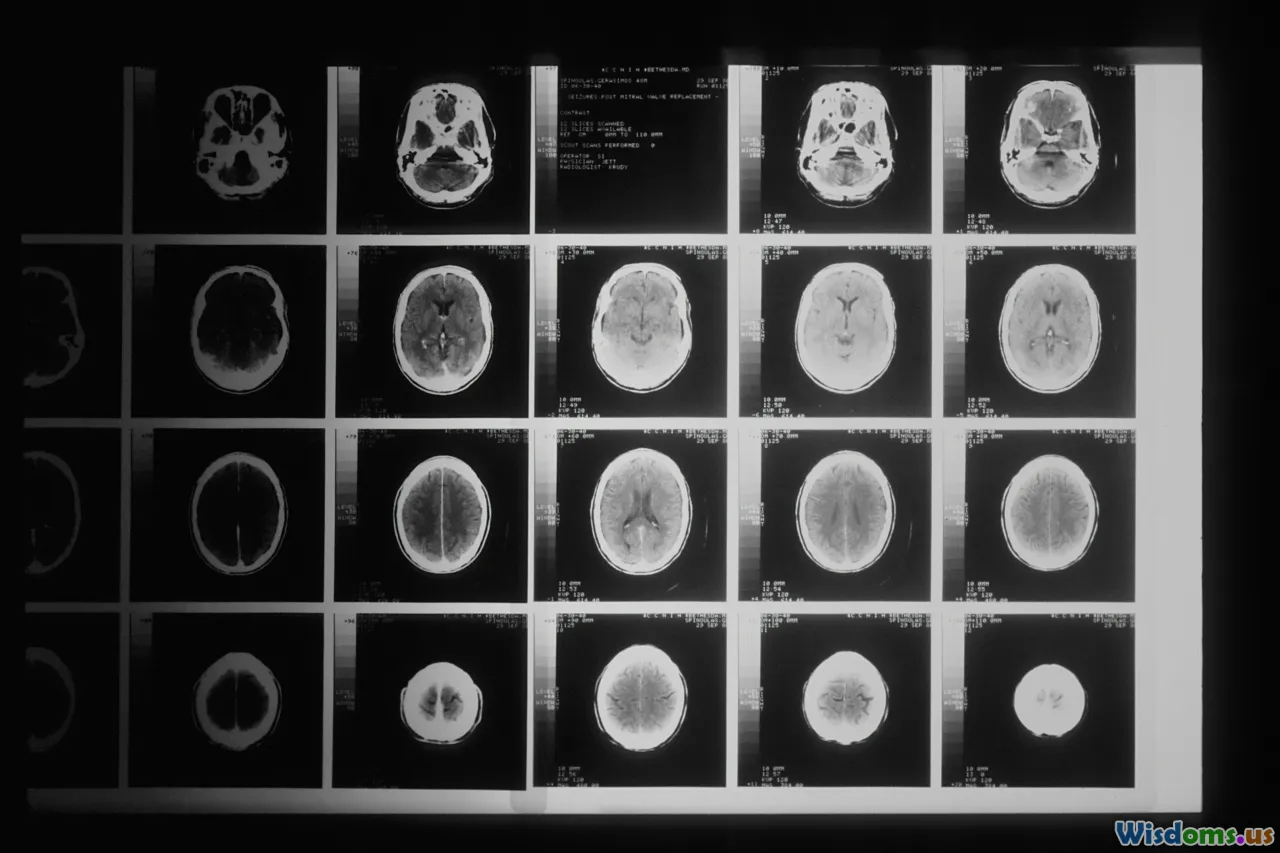

brain anatomy, hemispheres, neuroimaging, cerebral cortex

Both hemispheres of the cortex appear physically symmetrical, yet their functional specializations are strikingly asymmetrical. The left hemisphere traditionally takes the lion's share of direct language-related processing, but the right plays a subtle, equally vital role.

developing brain, left-handed, child neurology, MRI scans